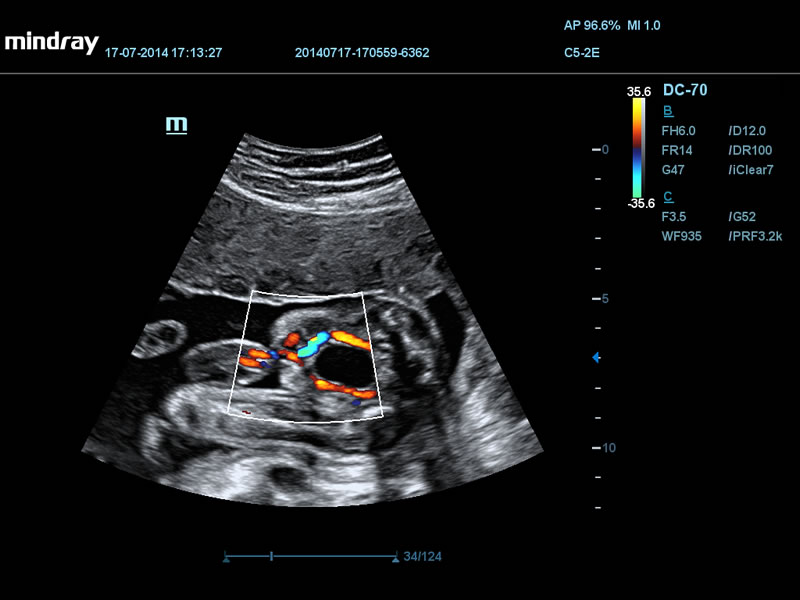

Сброс крови через овальное окно